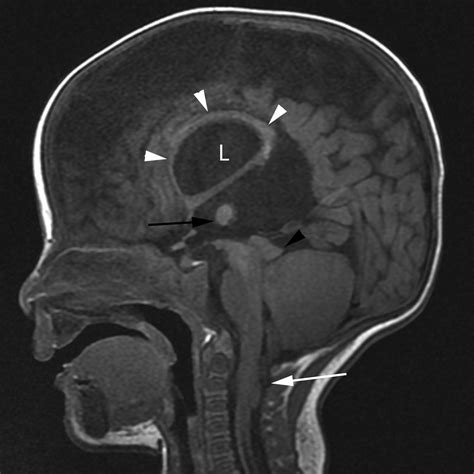

At its core, Chiari Type 2 involves the downward displacement of the cerebellar tonsils, the brainstem, and the fourth ventricle through the foramen magnum, which is the large opening at the base of the skull. This displacement creates a bottleneck effect that interferes with the normal flow of cerebrospinal fluid (CSF). Because this condition is developmental, it typically manifests in infants, as the structural abnormalities are present from birth.

The primary concern with this malformation is the obstruction of CSF circulation, which frequently leads to hydrocephalus—a condition where fluid accumulates in the brain, causing increased intracranial pressure. The structural interplay between the spine and the skull in these patients necessitates a highly coordinated medical approach involving neurosurgeons, pediatricians, and specialized therapists.

• Hydrocephalus Indicators: A rapidly increasing head circumference, bulging fontanelle, and irritability are common signs.

MRI (Magnetic Resonance Imaging) Provides detailed images of the cerebellum, brainstem, and spinal cord to assess the degree of herniation.

Ultrasound Frequently used in infants to monitor ventricular size and the progression of hydrocephalus.